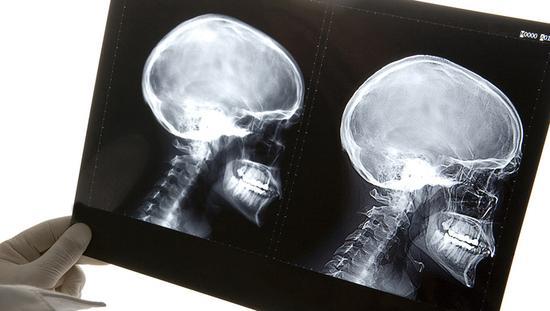

据英国《每日邮报》17日报道,意大利都灵高级神经调节小组的神经外科专家塞尔吉·卡纳瓦罗(Sergio Canavero)宣布,世界首例人类头部移植手术近日已被他在一具遗体上成功实施,手术在中国哈尔滨医科大学进行,历时18小时,任晓平教授参与指导了该手术。专家小组在奥利地首都维也纳的新闻发布会上表示,目前他们可能已经成功找到了头颅移植手术中重新连接脊椎、神经、血管的方式,他们很快将在申请参加试验的患者身上进行类似手术尝试。

消息一出,引发全球轩然大波。解放日报·上观新闻记者就此采访上海交通大学医学院附属瑞金医院神经外科主任卞留贯,他表示,从技术层面来看,头部移植手术为复合组织移植手术,复杂程度非同一般,“相比肢体移植手术,脑组织对缺血的耐受性更差,同时对中枢神经系统的连接有极大挑战,脊髓缝合更是难上加难。此外,术后还需要注射大量免疫抑制剂,防止免疫排斥反应等。”

“对于这一结果,我们拭目以待。”神经外科学界的诸多专家对此保持观望态度,然而作为全球最大的神经外科学术组织,世界神经外科联合会(WFNS)却为此发表了严肃声明,其中明确指出,施行头颅移植的技术具有一定可能性,但目前,只是能在人体头颈必需的脑血管吻合基础上建立脑血液循环,由于脊髓横断后,头与身体不能建立神经联系,人们仍没有能力做脊髓离断后的神经原再生。“因此,头颅移植不但在伦理学上不可接受,在科学方面也毫无意义。”